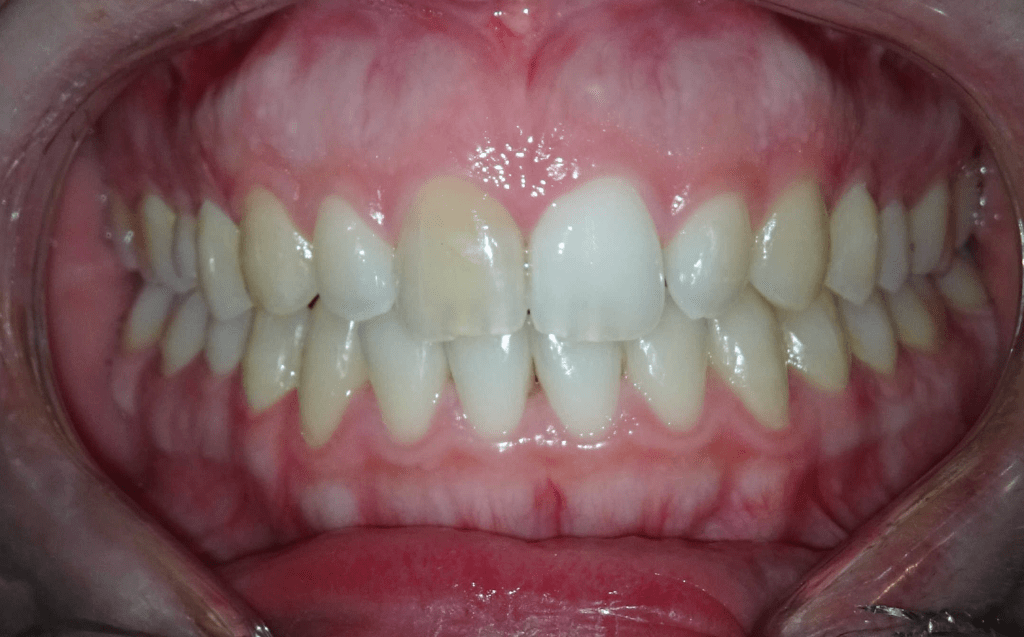

Pulpotomía biodentine + reco preendio